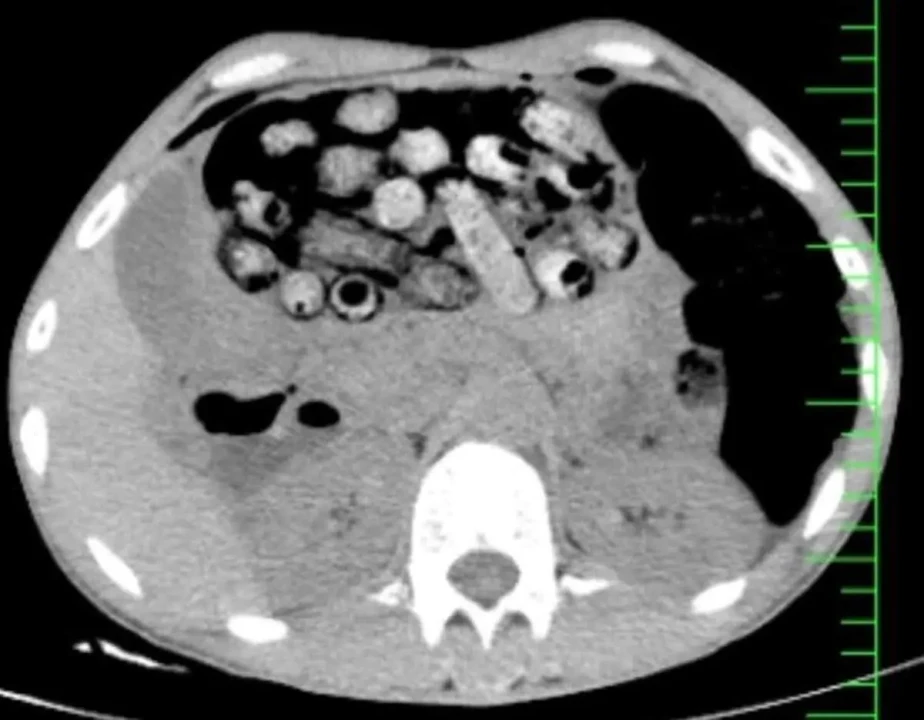

براساس اطلاعات اولیه مأمور همراه، بیمار پیش از مراجعه، اقدام به بلع تعدادی بسته محتوی مواد مخدر کرده بود. در پی انجام تصویربرداری فوری، تعداد زیادی بسته مشکوک در معده و روده کوچک و بزرگ وی مشاهده شد.

با توجه به خطر بالای پارگی احتمالی بستهها و بروز عوارض تهدیدکننده حیات، بیمار بلافاصله به اتاق عمل منتقل شد و جراحی سنگین وی از ساعت سه بامداد آغاز شد.

در این جراحی که به سرپرستی دکتر سامان شیخی، عضو هیأت علمی گروه جراحی عمومی دانشگاه علوم پزشکی البرز و با همکاری تیمهای اورژانس، تصویربرداری، بیهوشی و جراحی انجام و 90 بسته از معده و روده بیمار خارج شد.